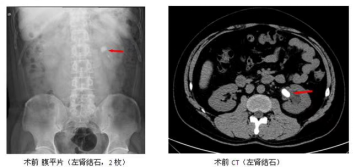

擅長腎結(jié)石、輸尿管結(jié)石、膀胱結(jié)石等泌尿系結(jié)石的微創(chuàng)治療(輸尿管鏡碎石、經(jīng)皮腎鏡 碎石、腹腔鏡取石等),目前95%以上結(jié)石已無需開刀手術(shù);擅長前列腺增生(肥大)的 經(jīng)尿道等離子剜除術(shù)微創(chuàng)治療;擅長腎囊腫、腎結(jié)核、腎上腺腫瘤、精索靜脈曲張、腎腫 瘤、膀胱腫瘤、前列腺腫瘤等疾病的腹腔...